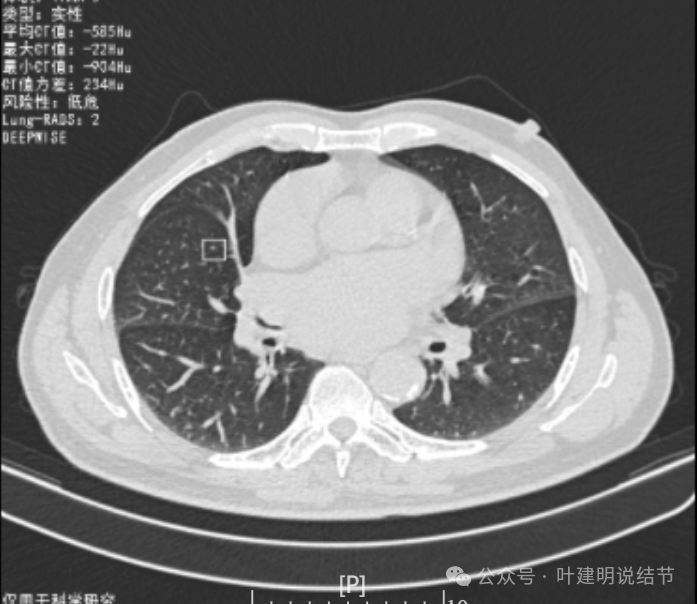

你的结节,对比各次的影像,原来的肺多发结节主要病灶是右上叶与左下叶这两处,其他过小。直到2022年8月,右下这处均不明显的。2023年没查,今年突然发现。首先几点:1、原有的结节没有明显进展,实性且小,考虑是良性的;2、右下结节原来没有,这次检出是新发的;3、两肺多发结节必不是右下这处新检出的病灶转移的(因为它们原来就有,右下这处是新发的)。右下这处的特点则有以下几点:1、病灶实性密度,磨玻璃成分不明显,但总体上并不是具有强收缩力或显著膨胀性的,与恶性程度很高的肺癌似乎不符合;2、表面不平毛糙,但毛刺样征并不锐利,紧邻胸膜也无明显胸膜牵拉凹陷,不是典型恶性的影像表现;3、口服消炎无好转,不像普通急性炎症;4、纵隔窗上见病灶内部密度低,周围的密度高些,中间更像坏死或液性密度。但这么小的肿瘤容易中间缺血性坏死吗?显然这与肿瘤恶性程度高而中间乏血供而坏死是不符合的。而这种表现与肉芽肿性炎伴坏死比较符合;5、病灶与胸膜紧邻,胸膜侧在纵隔窗上见基较宽并有胸膜增厚,这与炎性改变更为符合。我的感觉总体上倾向肉芽肿性炎可能性大,建议完善结核与隐球菌方面检查,并同时CT引导下穿刺活检(这个位置穿刺容易也风险小,又能取得病灶依据)。若有结核或隐球菌方面阳性结果,请内科医生按相应结果治疗;若均阴性,且穿刺也未见癌细胞,则可考虑3个月左右复查随访,当然也可直接局部胸腔镜下局部切了化验,既达诊断目的,也去除病灶。这要你自己酌情考虑选择。意见供参考!